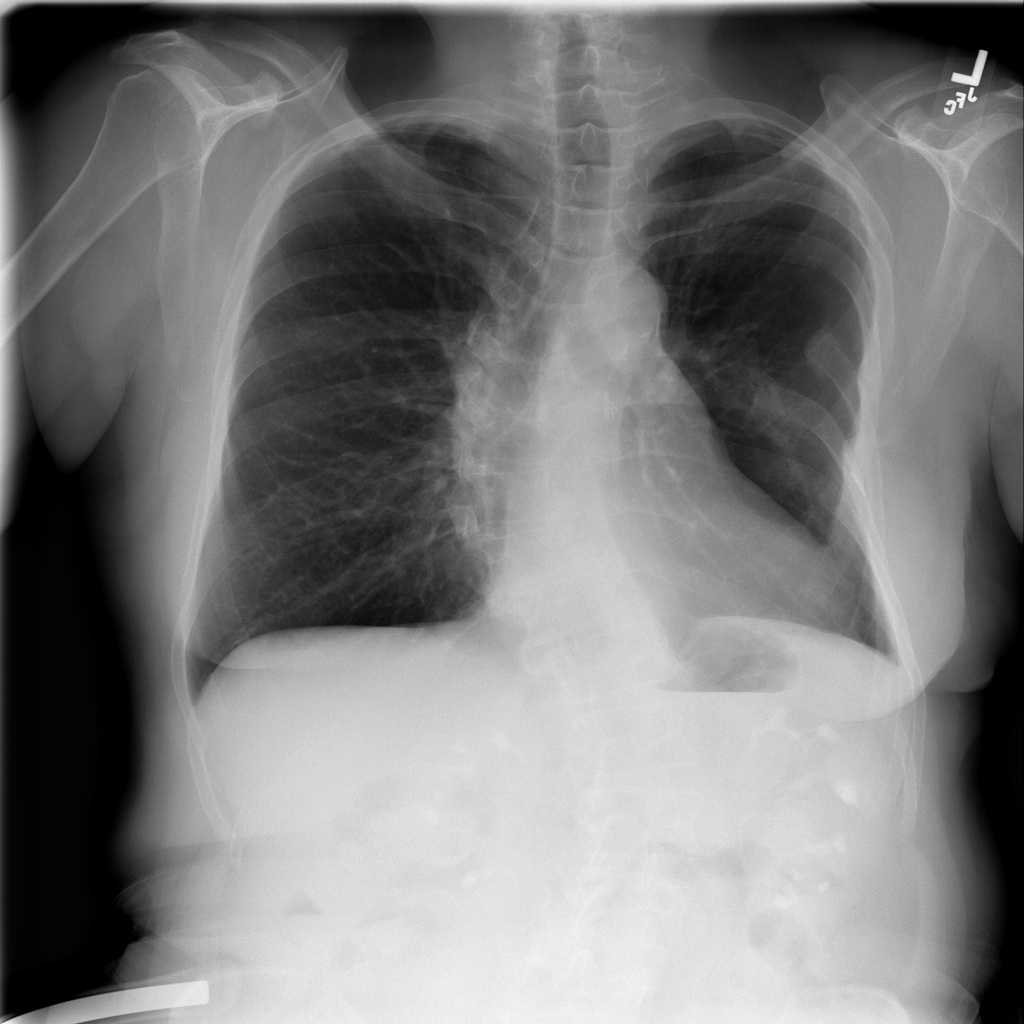

Showing up to 90 reference images for Fibrosis.

PAT-E066 · IMG-010Fibrosis

PAT-E066 · IMG-010

PA